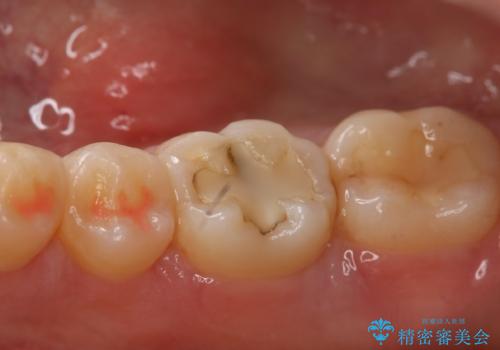

- 右下奥歯の虫歯治療を希望された患者様です。

保険の材料が劣化し、直下で虫歯の存在が確認出来ました。

セラミックを希望されたので形態・切削量を考慮し、セラミックインレーでの治療を計画しました。

虫歯が広く進行していましたが神経には到達していなかったので、予定通りセラミックインレーでの治療を行いました。